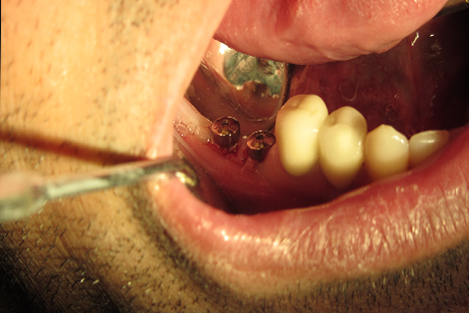

Post n Core